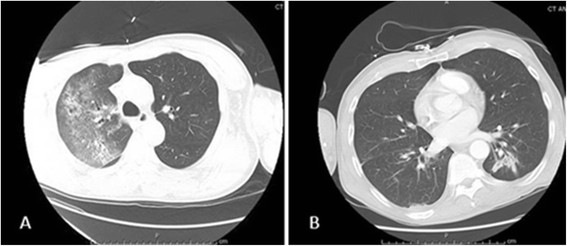

A 61 year-old homeless African-American male was admitted to the intensive care unit with fever, dyspnea, and hemoptysis for four days. He had a history of depression and active intravenous drug use. Physical examination was positive for crackles in both lung fields. He had no track marks on his skin. His white blood cell (WBC) count was 0.3 × 103/μL with absolute neutrophil count 100/mm3. Urine toxicology screen was positive for opiates and benzodiazepines. His basic metabolic panel was normal but his arterial blood gas (ABG) analysis revealed a PaO2 of 62 mm Hg on room air. He was intubated in the emergency room for hypoxia. Computed tomography (CT) scan of the chest revealed large patchy opacities in the right upper and middle lobes consistent with pneumonia and no evidence of pulmonary embolism (Figure 1A). Empiric vancomycin and piperacillin-tazobactam were started. His initial blood cultures and serum HIV ELISA antibody were negative. Three tracheal aspirate specimen smears were negative for acid-fast bacilli.

Figure 1.

Computed tomography of the chest. A. Patchy opacities inthe right lung. B. Resolution of the opacities after intravenous Amphotericin B.

A diagnosis of isolated pulmonary valve endocarditis secondary to Candida was made. Cardiothoracic surgery was consulted; they advised medical therapy and later re-evaluation as the patient was a high-risk candidate for surgery. Blood cultures obtained on hospital day 16 had no growth. After a tracheostomy was performed, the patient was transferred to a nursing home to complete liposomal amphotericin B for a total of eight weeks. His repeat CT chest at the time of discharge showed complete resolution of pulmonary infiltrates (Figure 1B) and he was weaned to tracheal mask. Lifelong suppressive oral fluconazole therapy was recommended. After eight weeks of antifungal therapy, a repeat TEE did not show any pulmonary valve vegetation (Figure 2B). The patient clinically improved, his tracheostomy was closed, and he was discharged back to the shelter. Six months after discharge, the patient was asymptomatic and doing well. He had stopped taking his oral fluconazole despite recommendations for lifelong suppressive therapy.